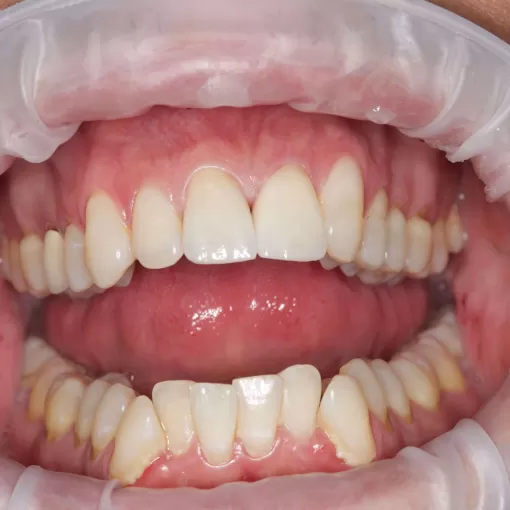

Пациент обратился с целью имплантации в области отсутствующего зуба 4.6. Однако после КЛКТ (3Д) исследования был обнаружен воспалительный процесс (киста) в области соседнего зуба 4.7 (рис. 1).